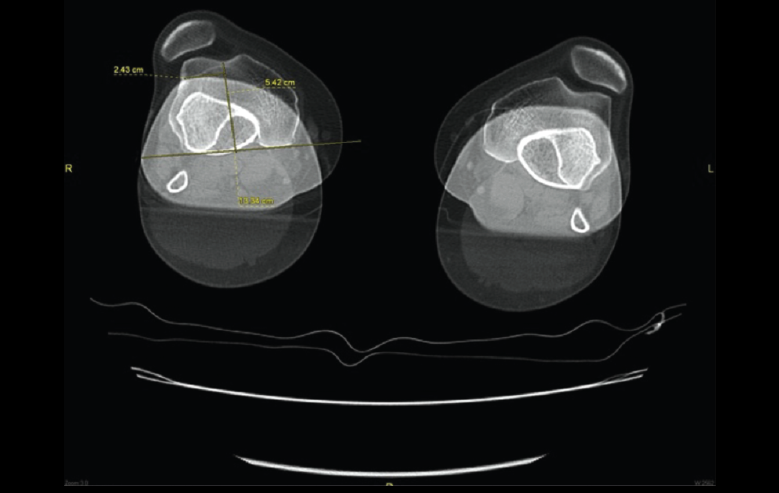

5.1. TA-GT (tuberosidad tibial anterior-garganta de la tróclea)

En pacientes sintomáticos con inestabilidad rotuliana, la TAC es útil para medir la TA-GT(10). La distancia TA-TG es una medida radiológica propuesta por Goutallier y Bernageau que sirve para cuantificar el ángulo Q. Consiste en medir la distancia en milímetros de la tuberosidad tibial anterior a la garganta de la tróclea proyectadas sobre una línea que pasa por los bordes posteriores de ambos cóndilos femorales, superponiendo 2 cortes axiales de TAC. Es una medida fiable y reproducible pero poco precisa, con un margen de error de más de 4 mm. La distancia TA-GT es mayor de 20 mm en el 56% de las inestabilidades rotulianas y tan solo en el 3% de la población sana(11) (Figura 28).

5.2. Balance rotuliano

Mide la inclinación de la rótula en relación con el borde posterior de los cóndilos femorales (Figura 29).

Figura 28. Corte axial de tomografía axial computarizada con superposición de imágenes con rótula y parte posterior de cóndilos y tuberosidad tibial anterior, que nos permite medir la distancia TA-GT, en condiciones normales hasta 2 cm.

Figura 29. Corte axial de tomografía axial computarizada con superposición de imágenes con rótula y parte posterior de cóndilos y tuberosidad tibial anterior, que nos permite medir el tilt o balance rotuliano, en condiciones normales hasta 20°.